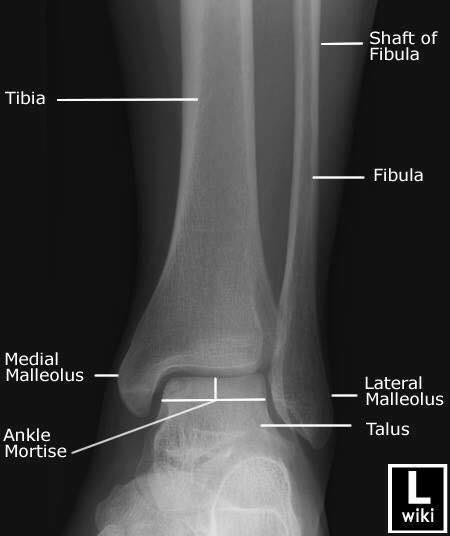

Las radiografías, generalmente llamadas rayos X, producen imágenes como sombras de huesos y ciertos órganos y tejidos. Las radiografías son muy buenas para detectar problemas óseos. Pueden mostrar algunos órganos y tejidos blandos; sin embargo, la MRI y la CT suelen crear mejores imágenes de los mismos. Aun así, las radiografías son rápidas, fáciles de obtener y menos costosas que los otros estudios, por lo que se pueden usar para obtener información rápidamente.

Un tubo especial dentro de la máquina de rayos X emite un haz de radiación controlada. Los tejidos del cuerpo absorben o bloquean la radiación en diferentes grados. Los tejidos densos como los huesos bloquean la mayor parte de la radiación, pero los tejidos blandos, como la grasa o los músculos, bloquean menos radiación. Después de pasar por el cuerpo, el haz alcanza una pieza de un fragmento de película o un detector especial. Los tejidos que bloquean altas cantidades de radiación, como los huesos, aparecen como áreas blancas en un fondo negro. Los tejidos blandos bloquean menos radiación y aparecen en tonos de gris. Los órganos que contienen principalmente aire (como los pulmones) aparecen en negro. Los tumores son por lo general más densos que el tejido que los rodea, por lo que suelen verse en tonos grises más claros.